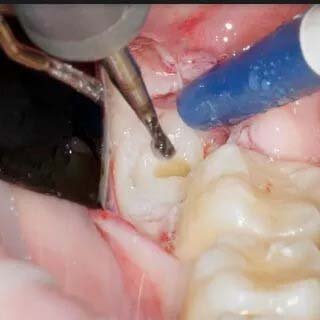

Marathon Straight Surgical Handpiece ES -100N

Straight surgical handpiece external water spray quick release

Marathon Straight Surgical Handpiece ES-100N is a precision instrument designed for surgical procedures in dentistry. With a sleek and durable titanium body, this handpiece ensures optimal performance and longevity. The handpiece boasts external water spray functionality, facilitating efficient cooling during operations. It is easily washable in a thermodisinfector and autoclavable at temperatures up to 135 degrees Celsius, ensuring strict infection control protocols are met. Operating at a maximum speed of 40,000 rpm/min, the low-speed handpiece features a 1:1 gear ratio, providing precise control during intricate dental procedures. Specifically designed for use with HP burs of Ø2.35, the direct drive mechanism enhances stability and accuracy. The compact dimensions of L88 x Ø17.5 (mm) and a weight of 75g contribute to ergonomic handling. The Marathon ES-100N embodies cutting-edge technology, making it an indispensable tool for dental professionals seeking reliability, versatility, and hygiene in their surgical equipment.

• Autoclavable: up to 135 degrees C

• Speed Max: 40.000 rpm min-1

• Dimensions: L88 x Ø17.5 (mm)

• Weight: 75g

• Gear Ratio: Low-speed handpiece 1:1 Ratio

• Direct Drive For HP burs: (Ø2.35)

• Body Material: Titanium